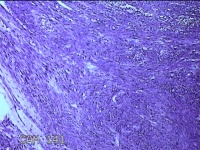

子宫肌瘤

性别

女

年龄

38岁

临床诊断

一般病史

发现子宫肌瘤复发7年余。

标本名称

大体所见

灰白粉红色结节样肿物8.5x5.5x4cm一个,表面糜烂,切面灰白色,编织状,质中。